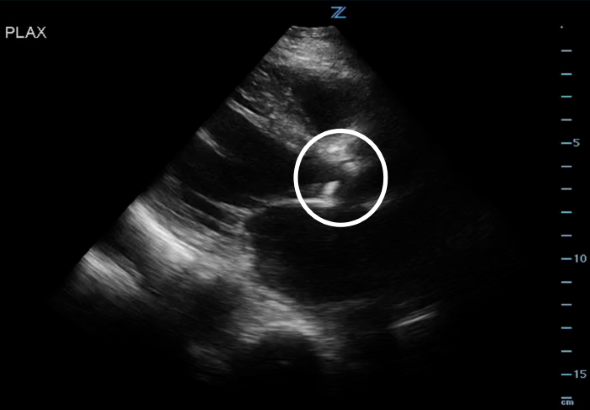

Figure 1. PLAX view showing the stenotic and calcified AV.

- Obtain a parasternal long axis (PLAX) and right ventricular outflow view (RVOT) and examine the aortic valve leaflets. Is there AV calcification? How’s the AV leaflet mobility? Is there also LV hypertrophy? Several studies have found that novice sonographers have been able to accurately pick up severe aortic stenosis.4-6

*Notice how calcified the AV leaflets are and how little the valve orifice opens.